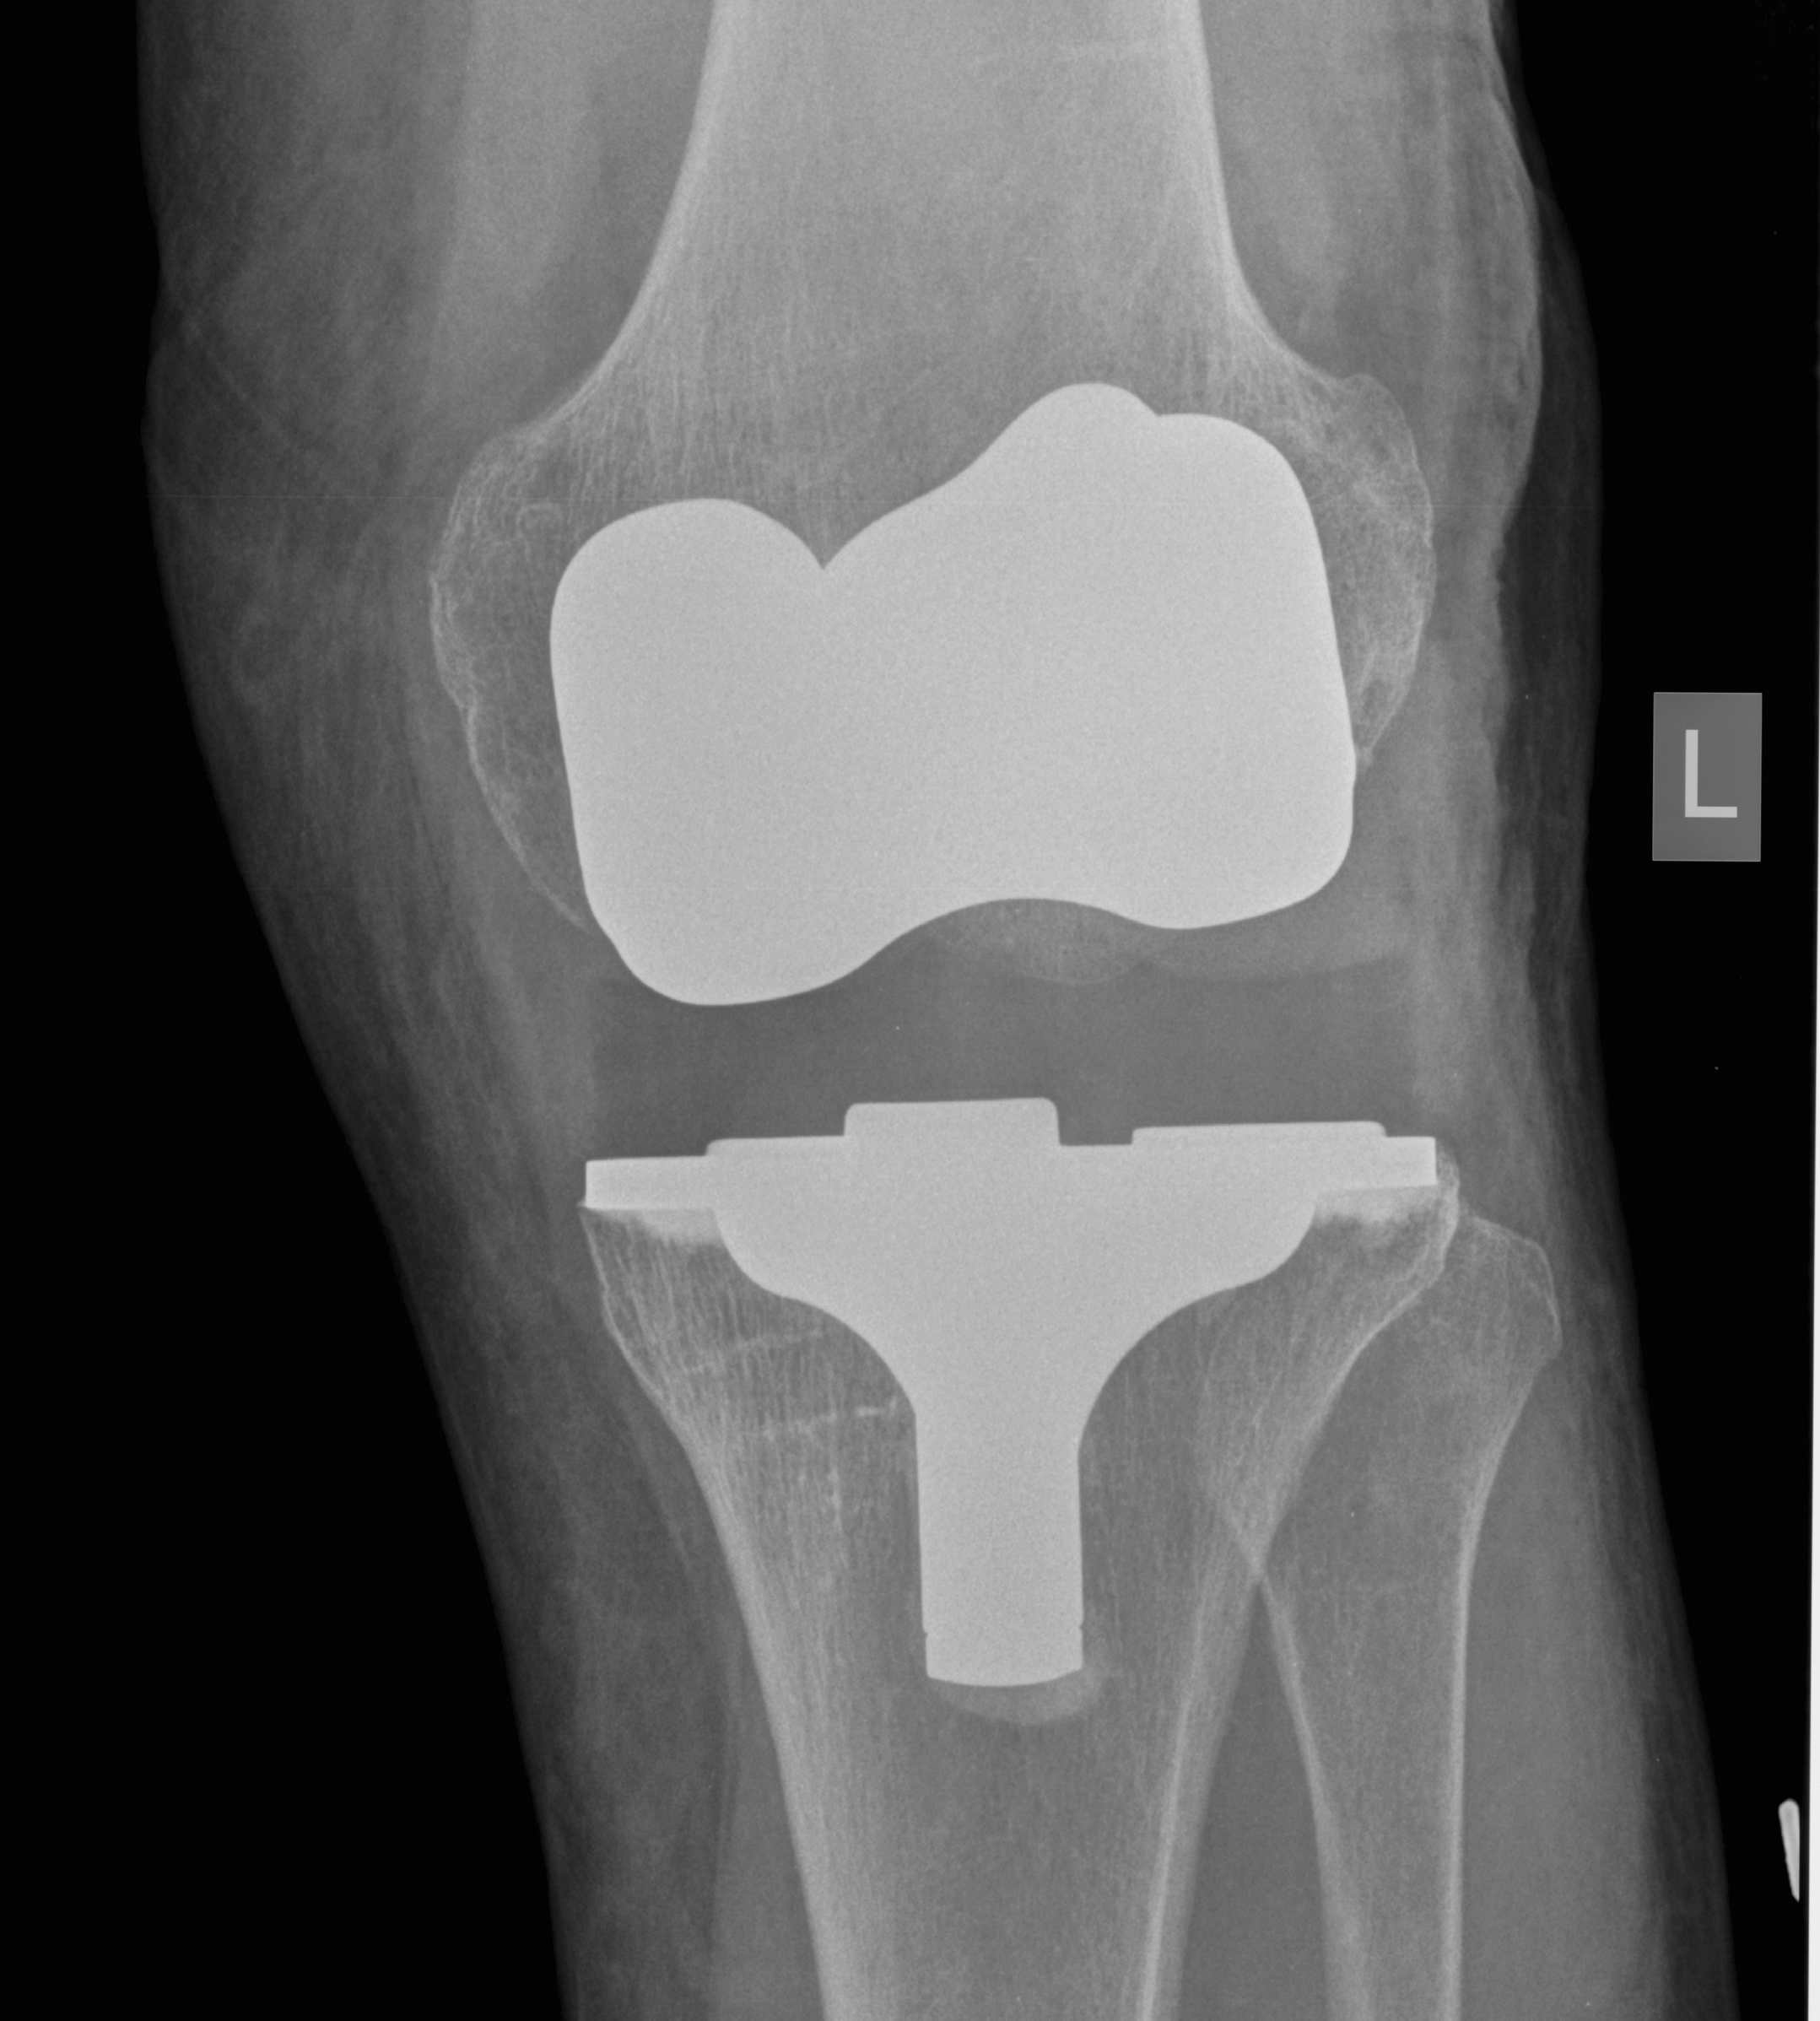

2. Varus Valgus Instability

Varus-Valgus instability